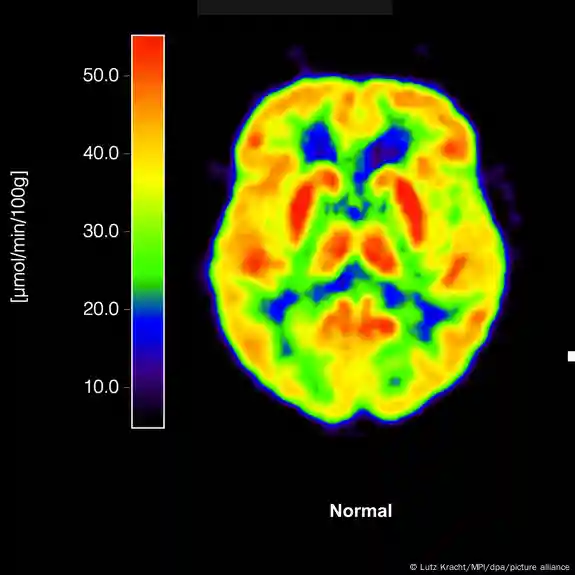

الزائمر کی بیماری بین الاقوامی سطح پر ڈیمنشیا کے مرض کی سب سے عام وجہ ہے اور اس کا تعلق پروٹینز کی ان دو مخصوص لیکن کلیدی اقسام سے ہے، جو دماغ میں پائی جاتی ہیں۔

ان میں سے ایک پروٹین کا نام ایمی لوئڈ (amyloid) ہے جبکہ دوسری ٹاؤ (tau) کہلاتی ہے۔ برطانیہ میں کیے جانے والے بلڈ ٹیسٹ تجربات میں ماہرین کی توجہ ٹاؤ نامی پروٹین کی ایک خاص ذیلی قسم 'پی ٹاؤ 217‘ پر مرکوز رہے گی۔